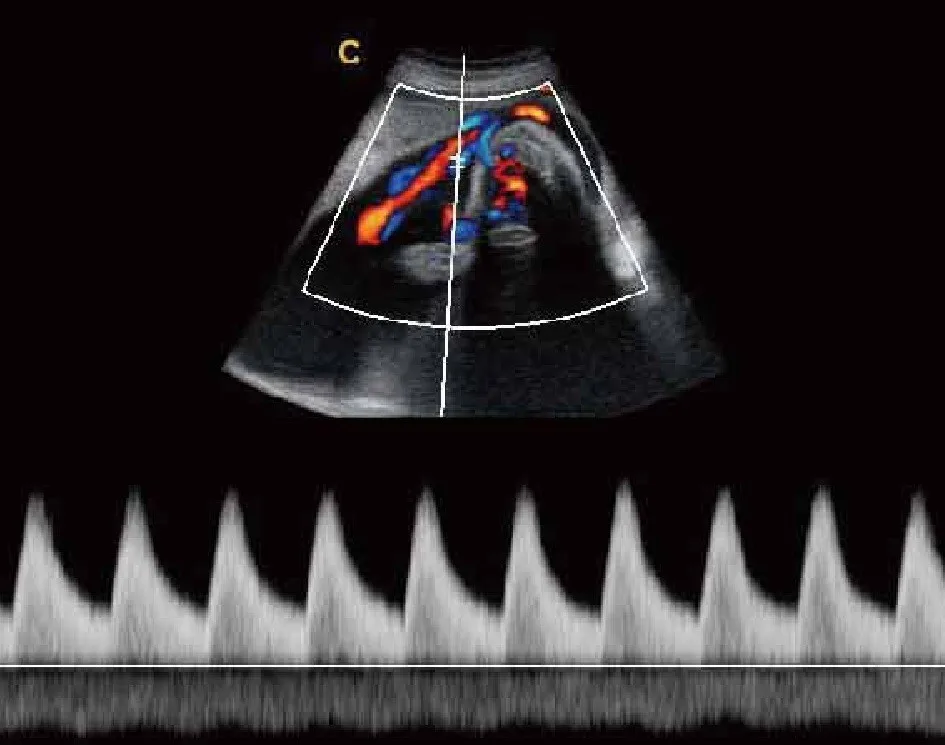

Pw режим

Pw режим 108 фотографий